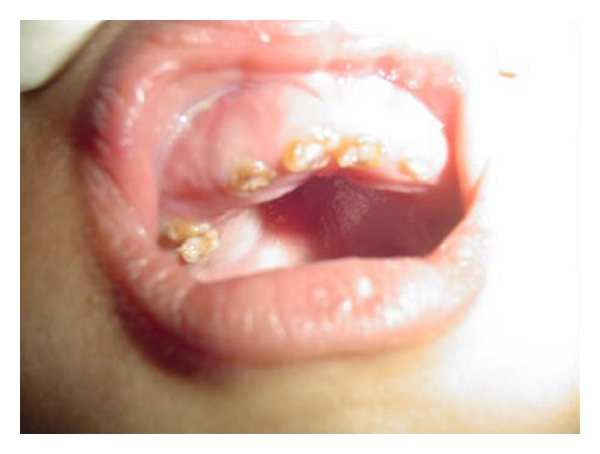

Patient’s elder brother who was 10 years old had a deformed growth with bowing in the upper and the lower limbs. He also reported of multiple fractures and frequent joint dislocations secondary to minor trauma. The dental findings were identical to that of the younger sibling, but there was no evidence of delayed eruption (Figure 5). Radiographs of the lower limbs revealed thinner cortices, bowing of the femur and tibia, and expanded metaphyses (Figures 6 and 7). Based on these features and the familial history, a diagnosis of osteogenesis imperfect (Type IV B) with dentinogenesis imperfecta was made. Because of logistical reasons, the patients could not continue the dental treatment in our institution.